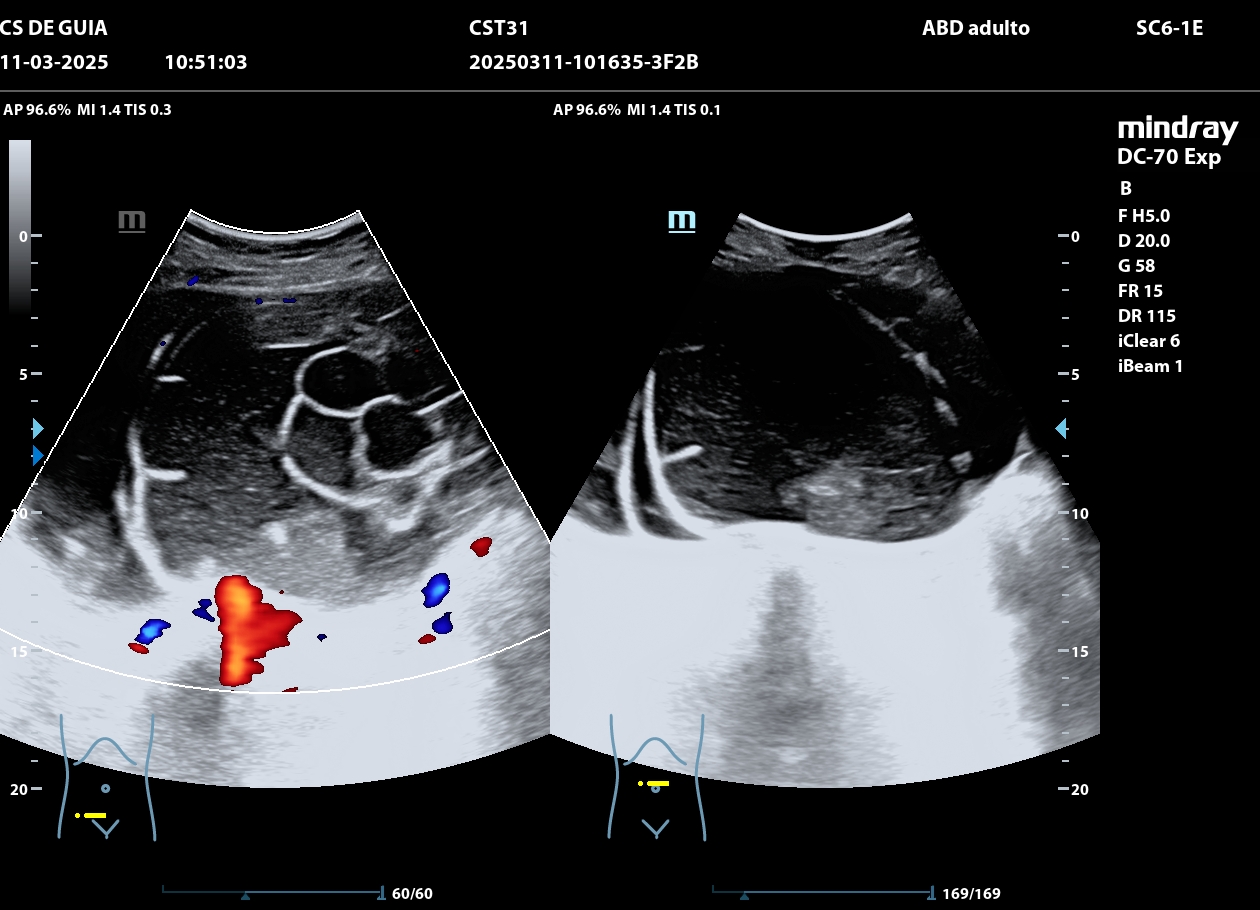

Se realiza ecografía clínica en consulta. Se observa lesión quística sin captación Doppler desde hipogastrio hasta mesogastrio compatible con cistoadenoma de ovarios (no se puede apreciar debido al gran tamaño si de anejo izquierdo o derecho), con útero sin alteraciones, no hidronefrosis.

La paciente fue derivada al Hospital donde tras realizar nuevamente ecografía: Útero en anteversión de bordes regulares. Endometrio lineal. Anejo derecho normal. A nivel de anejo izquierdo se objetiva formación que escapa alcance de sonda TV por lo que se completa examen vía ECO ABD. Formación multilocular de contenido sólido de baja densidad de 225*108*157 mm, con > 10 lóculos, componente sólido a expensas de confluencia de tabiques de 26 mm de diámetro máximo contenido de bajo nivel, sombra acústica presente. Doppler score 2-3 en tabiques. No líquido libre.